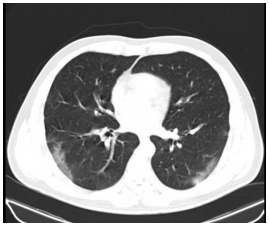

A imagem, abaixo, no corte tomográfico do tórax pode ser compatível com:

I. Pneumonia bacteriana. II. Pneumonia viral por influenza. III. Pneumonia organizante. IV. Pneumonia viral por covid-19.

Quais estão corretas?